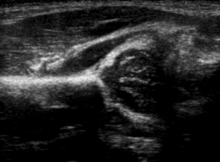

The condition can be confirmed by ultrasound[24] and X-ray.[25] Ultrasound imaging yields better results defining the anatomy until the cartilage is ossified. When the infant is around 3 months old a clear roentgenographic image can be achieved. Unfortunately the time the joint gives a good x-ray image is also the point at which nonsurgical treatment methods cease to give good results. In x-ray imaging dislocation may be indicated if the Shenton's line (an arc drawn from the medial aspect of the femoral neck through the superior margin of the obturator foramen[26]) does not result in a smooth arc. However, in infants this line can be unreliable as it depends on the rotation of the hip when the image is taken ([27])